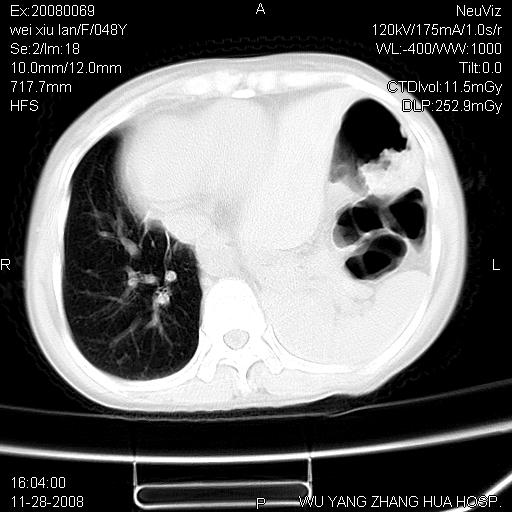

标题: CT16847:女,48岁,咳嗽,发热两日,平常偶有上腹部不适。 [打印本页]

标题: CT16847:女,48岁,咳嗽,发热两日,平常偶有上腹部不适。

能否考虑食管裂孔疝?请老师们多多指教。

这个是左侧膈膨升伴不完全性胃翻转,手术将松弛的左横膈膜折叠缝合即解决问题。

支持左侧膈疝,心脏受压右移.

左下肺不张、膈膨升,胸腔胃

胃、脾脏及部分肠管明显升高,并压迫心脏移位,

首先考虑:左侧膈疝。

左侧胸腔内见胃肠及脾脏影

支持膈疝